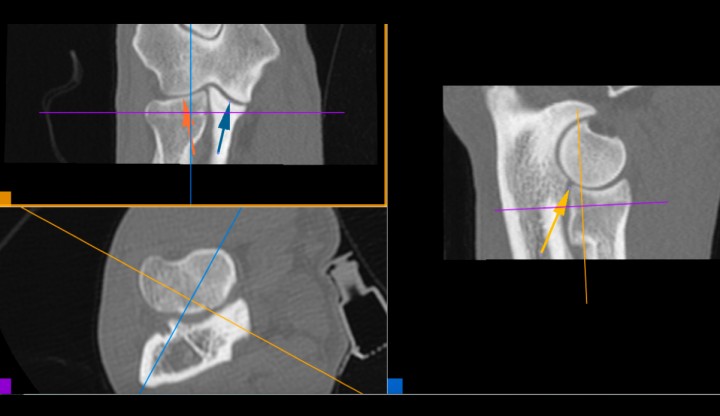

La valoración de la congruencia articular la realizamos con el visor Horos© mediante reconstrucciones ortogonales en 2D, partiendo del plano transversal y realizando reconstrucciones ortogonales con los ejes siempre perpendiculares entre sí (reconstrucción 2D ortogonal) (Fig. 12), y en casos dudosos inclinando los planos de corte y adaptándolos a la morfología de la apófisis coronoides medial (forma conocida como reconstrucción multiplanar en 3D), que nos proporciona una visión más exacta de la congruencia articular (Fig. 13) (Vídeo 5).

<p>Reconstrucción 3D MPR multiplanar. Esta forma de reconstrucción permite orientar los ejes según se desee. Cada eje tiene un color y produce la imagen correspondiente en el recuadro del mismo color. El eje marrón es tangencial a la ACM y ofrece la mejor vista para valorar la congruencia articular del codo. Espacio articular humero-radial (flecha roja), espacio articular húmero-cubital (flecha azul), escalón entre la apófisis coronoides lateral y la epífisis proximal del radio (flecha marrón).</p>

Figura 13

Reconstrucción 3D MPR multiplanar. Esta forma de reconstrucción permite orientar los ejes según se desee. Cada eje tiene un color y produce la imagen correspondiente en el recuadro del mismo color. El eje marrón es tangencial a la ACM y ofrece la mejor vista para valorar la congruencia articular del codo. Espacio articular humero-radial (flecha roja), espacio articular húmero-cubital (flecha azul), escalón entre la apófisis coronoides lateral y la epífisis proximal del radio (flecha marrón).